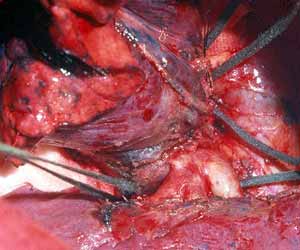

On occasion a sleeve resection of the upper lobe and the pulmonary artery is necessary (Figure 16). Pulmonary artery and inferior pulmonary vein control are obtained as described above. The vascular conduit is constructed from a segment of autologous pericardium (Figure 17). When sizing the conduit, two points must be considered: the PA stumps can be approximated closer than it seems, and the conduit will stretch more than predicted. It is advisable to tailor the length of the conduit on the basis of the resected arterial segment, because the elasticity of the two tissues is comparable. The bronchial anastomosis is performed first to avoid traumatizing the PA (Figure 18). The PA is reconstructed by end-to-end anastomosis with running 5/0 or 6/0 monofilament suture (Figure 19).